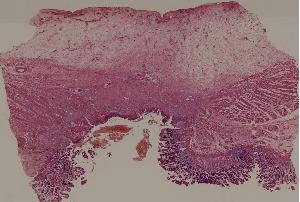

60. Gastric ulcer

61. Gastric adenocarcinoma(Mucinous adenocarcinoma of the stamoch)